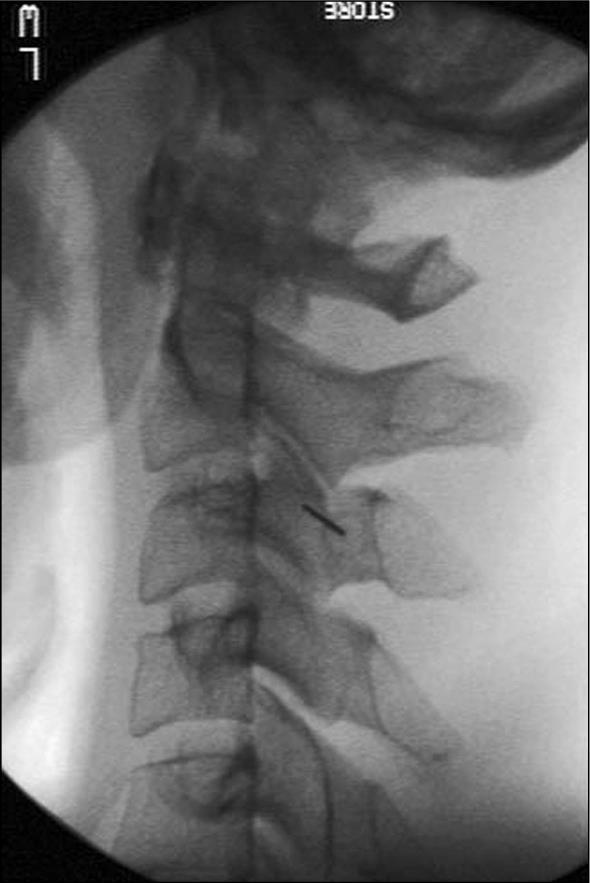

Patients were tested for facet joint pain with an MBB with about 1 ml of bupivacaine (0.25%) and 20 mg triamcinolone. Injections were performed with fluoroscopic visualization using established techniques 28. A lateral view of the spine was obtained. The target point is the centroid of the articular pillar with the same segmental number as the target nerve. The needle is placed straight along the x-ray beam to the medial branch (Figure 1). Target joints were identified by the pain pattern, local tenderness over the area, and provocation of pain with deep pressure.

Figure 1.Lateral fluoroscopic view with the needle in position for a C3 medial branch block.